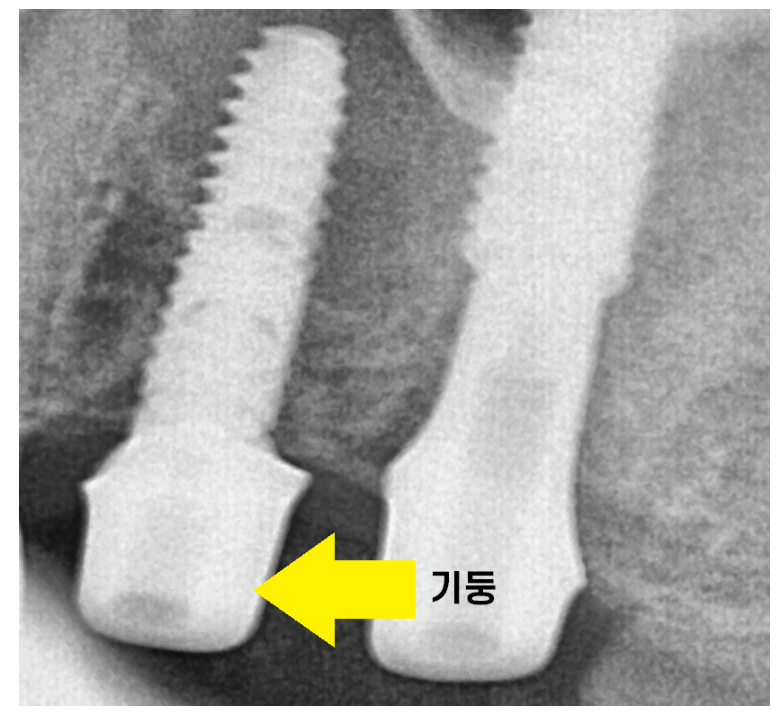

임플란트와 보철을 연결하는 기둥을 제작하고

기둥 위에 올라가는 보철물을 본을 뜹니다.